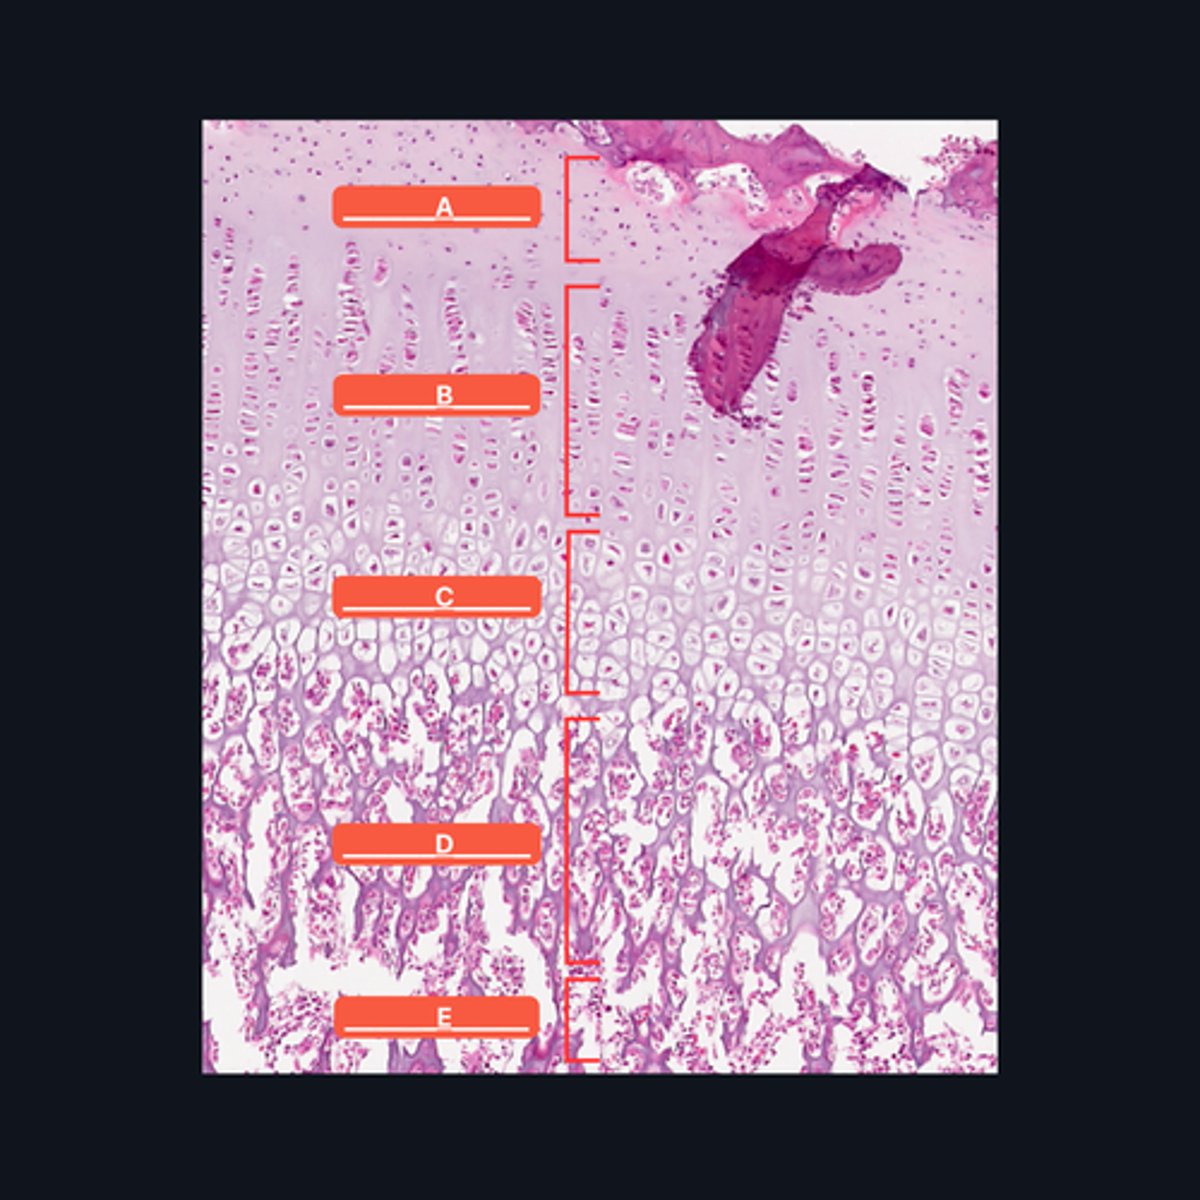

A - Zone of Resting Cartilage Cells

B - Zone of Proliferation

C - Zone of Maturation

D - Zone of Calcification

E - Zone of Ossification

Identify the pointed structures

B - Zone of Proliferation

Which pointed structure is the zone where instestitial growth occurs and what zone is it?

E - Zone of Ossification

Which pointed structure and what zone where many of the cavities left by cartilage cells merge to form marrow cavities?

C - Zone of Maturation

Which pointed structure and what zone do not divide anymore?

A - Zone of Resting Cartilage Cells

Which pointed structure and what zone anchors the epiphyseal plate to the epiphysis?

D - Zone of Calcification

Which pointed structure and what zone where the cartilage matrix is calcified